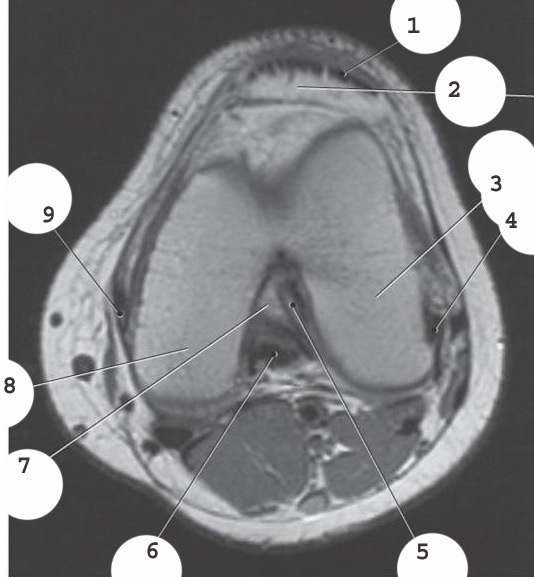

1

Quadracep group

2

hamstring group